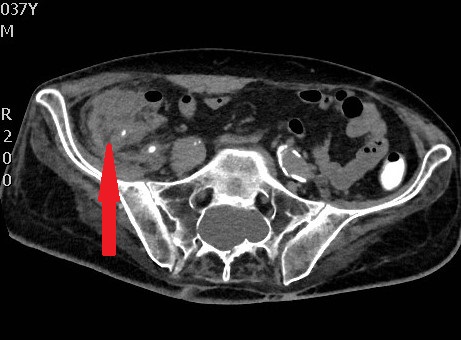

CT scan κοιλίας. Παρουσία ασβεστώσεων, κυστικο-συμπαγών περιοχών και λιπώδους ιστού, ενδεικτικά τερατώματος δεξιάς πλευράς (Ευγενική παραχώρηση Dr. V. Penopoulos)